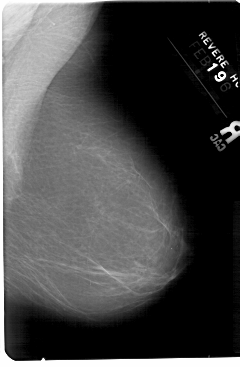

A_1346_1.LEFT_CC

LEFT_CC LINES 5476 PIXELS_PER_LINE 3166 BITS_PER_PIXEL 12 RESOLUTION 43.5 OVERLAY